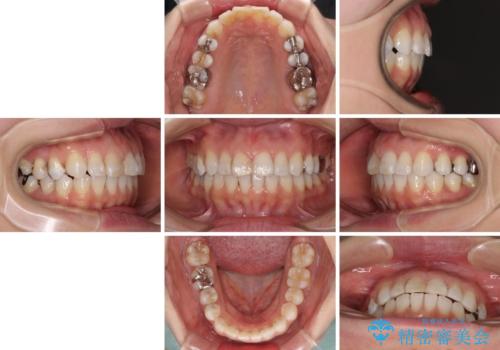

- 前歯のデコボコを治したいとのことで来院された患者様です。

上下顎ともに歯列全体の後方移動とIPR(歯と歯の間を削る)によってデコボコが解消するように設計し、インビザラインにより治療を行うこととしました。

しっかりと装着時間を守ってくださったのですが、途中妊娠にともなう悪阻や出産といったイベントがあり、予定よりも治療期間が長くなりました。